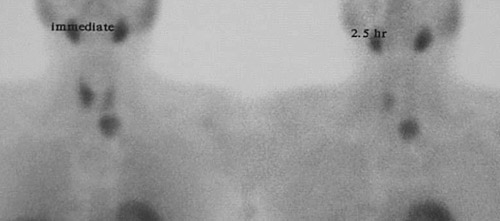

![]() | This parathyroid scan following intravenous administration of Tc99 demonstrates immediate radiotracer uptake in salivary glands, heart, and thyroid lobes, as well as an area of uptake below the left thyroid lobe consistent with a parathyroid adenoma. At 2.5 hours, the activity in thyroid gland has washed out, and a second focus of activity appears inferior to the right lobe of thyroid, representing another parathyroid adenoma. Double adenomas represent less than 1% of cases of parathyroid adenoma. |